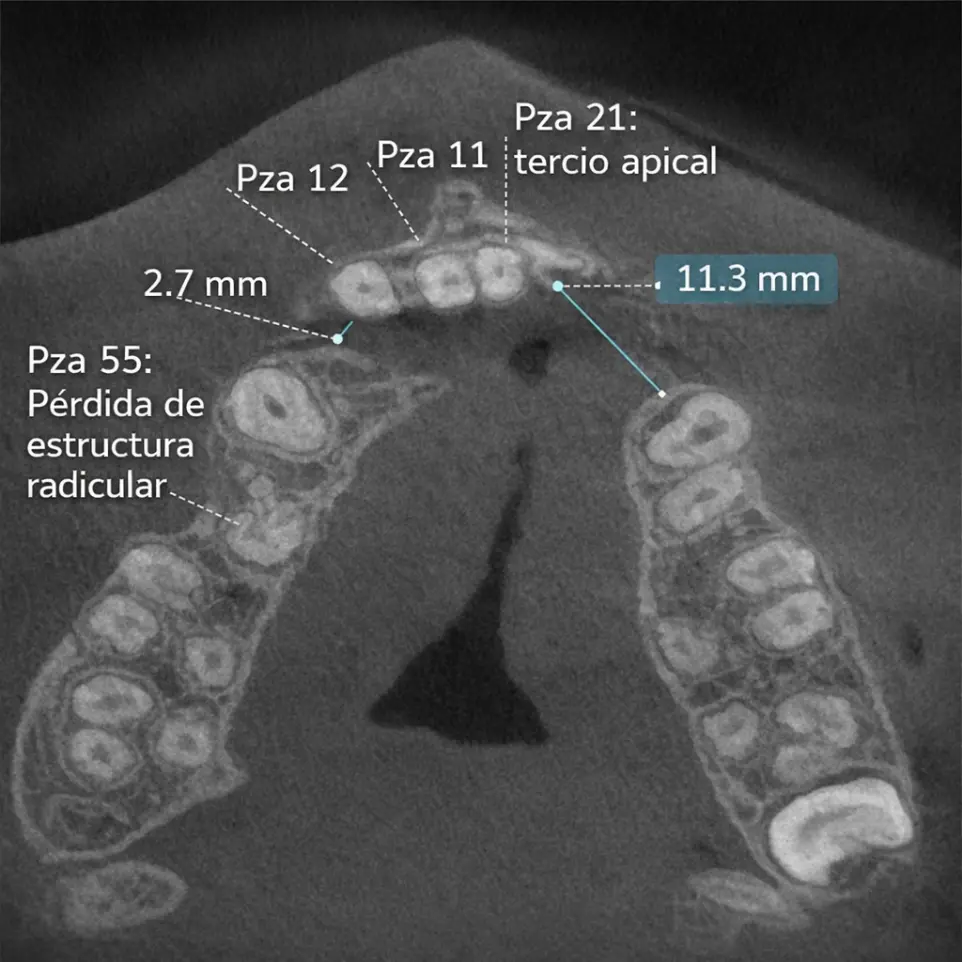

TOMOGRAFÍA DE DIENT​ES RETENIDO

Se da en casos de dientes que no completaron su proceso de erupció​n y su ubicación es compleja.